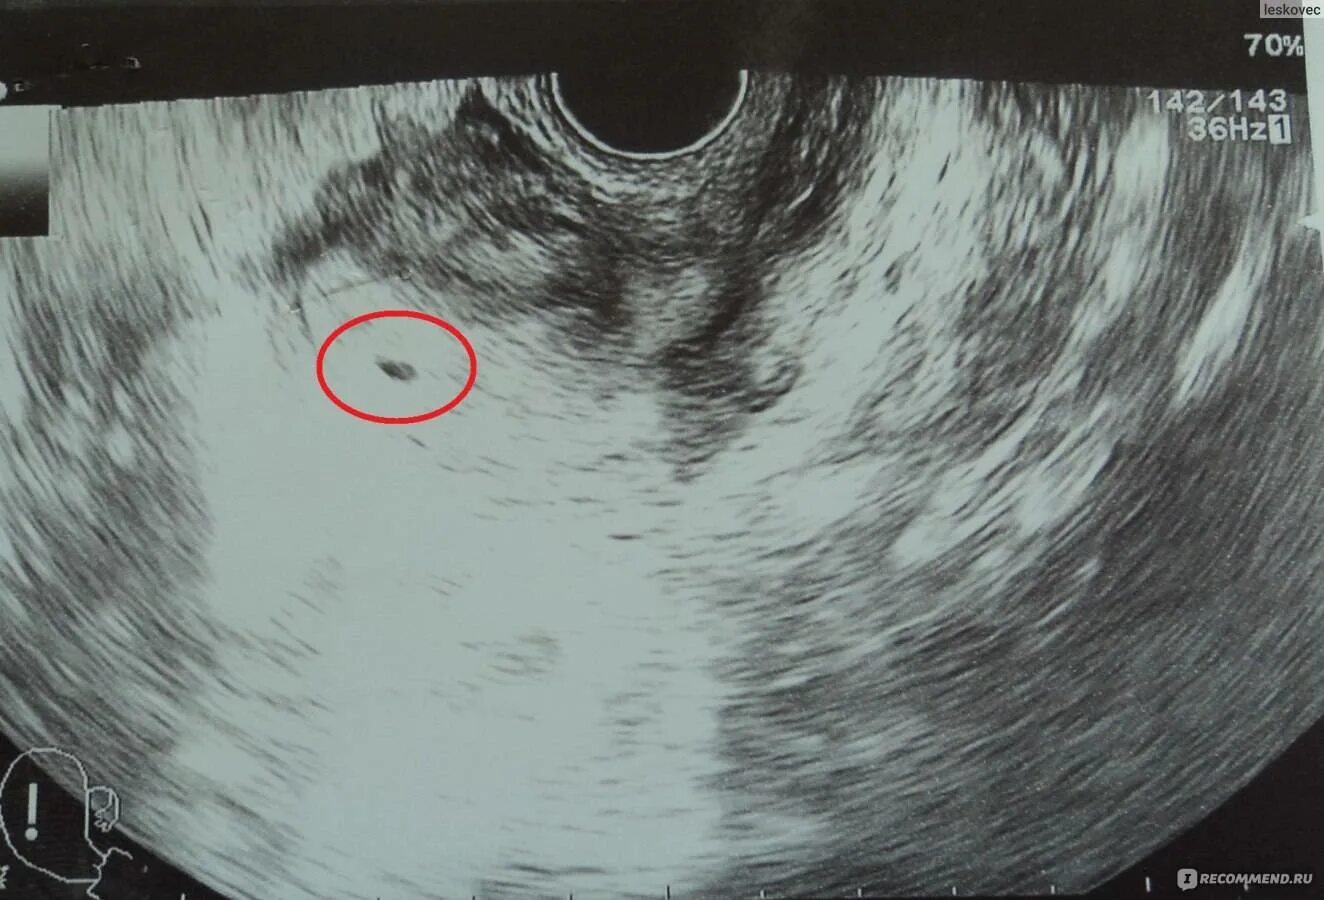

Беременна 2 недели срок